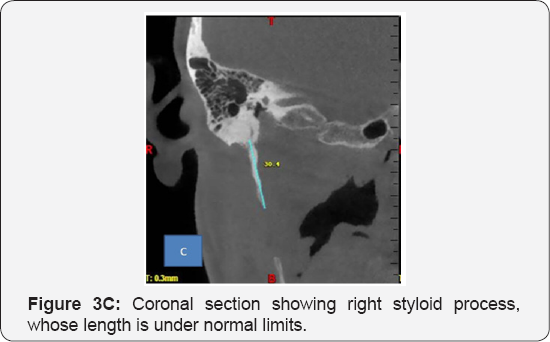

Based on the history and clinical findings, a provisional diagnosis of Myofacial Pain Dysfunction Syndrome was put forth. And Eagles syndrome was considered under differential diagnosis. Panoramic radiograph showed that the length of left styloid process to be 48mm, with Langlais type I pattern (Figure 2). Considering the elongated styloid process and suspecting eagle's syndrome, CBCT was advised. CBCT scan showed unilateral elongation of the styloid process towards the left. The actual length of the styloid process was processed using CBCT in various sections (Figure 3A-3D), and was found to be 62.2mm in comparison with the OPG, which was 48mm. Almost a difference of14mm was noticed between the two modalities. Hence showing, CBCT as the most reliable radiologic modality, to be carried out in cases where styloid process elongation is suspected. Based on the history, clinical findings and investigations, a final diagnosis of Eagles Syndrome was given and the patient was referred, for the removal of the styloid process.

The most reliable radiological investigation in recent times is the CBCT, where the exact length and extent of the styloid process can be studied. This syndrome may be treated conservatively or surgically. Conservative treatment includes transpharyngeal injection of steroids with lignocaine, nonsteroidal antiinflammatory drugs, diazepam, application of heat, traditional chinese medicines, and transpharyngeal manipulation by manually fracturing the styloid process. The most satisfactory, effective and followed treatment is surgical shortening of the styloid process, either through an intraoral or external approach. Advantage of an external approach is the proper exposure of the styloid process and the adjacent structures, and this advantage outweighs all the other considerations and also facilitates the resection of a partially ossified stylohyoid ligament. Transoral resection prevents outside scars, but carries the risk of deep cervical infection with possible injury to the neurovascular bundles [10].